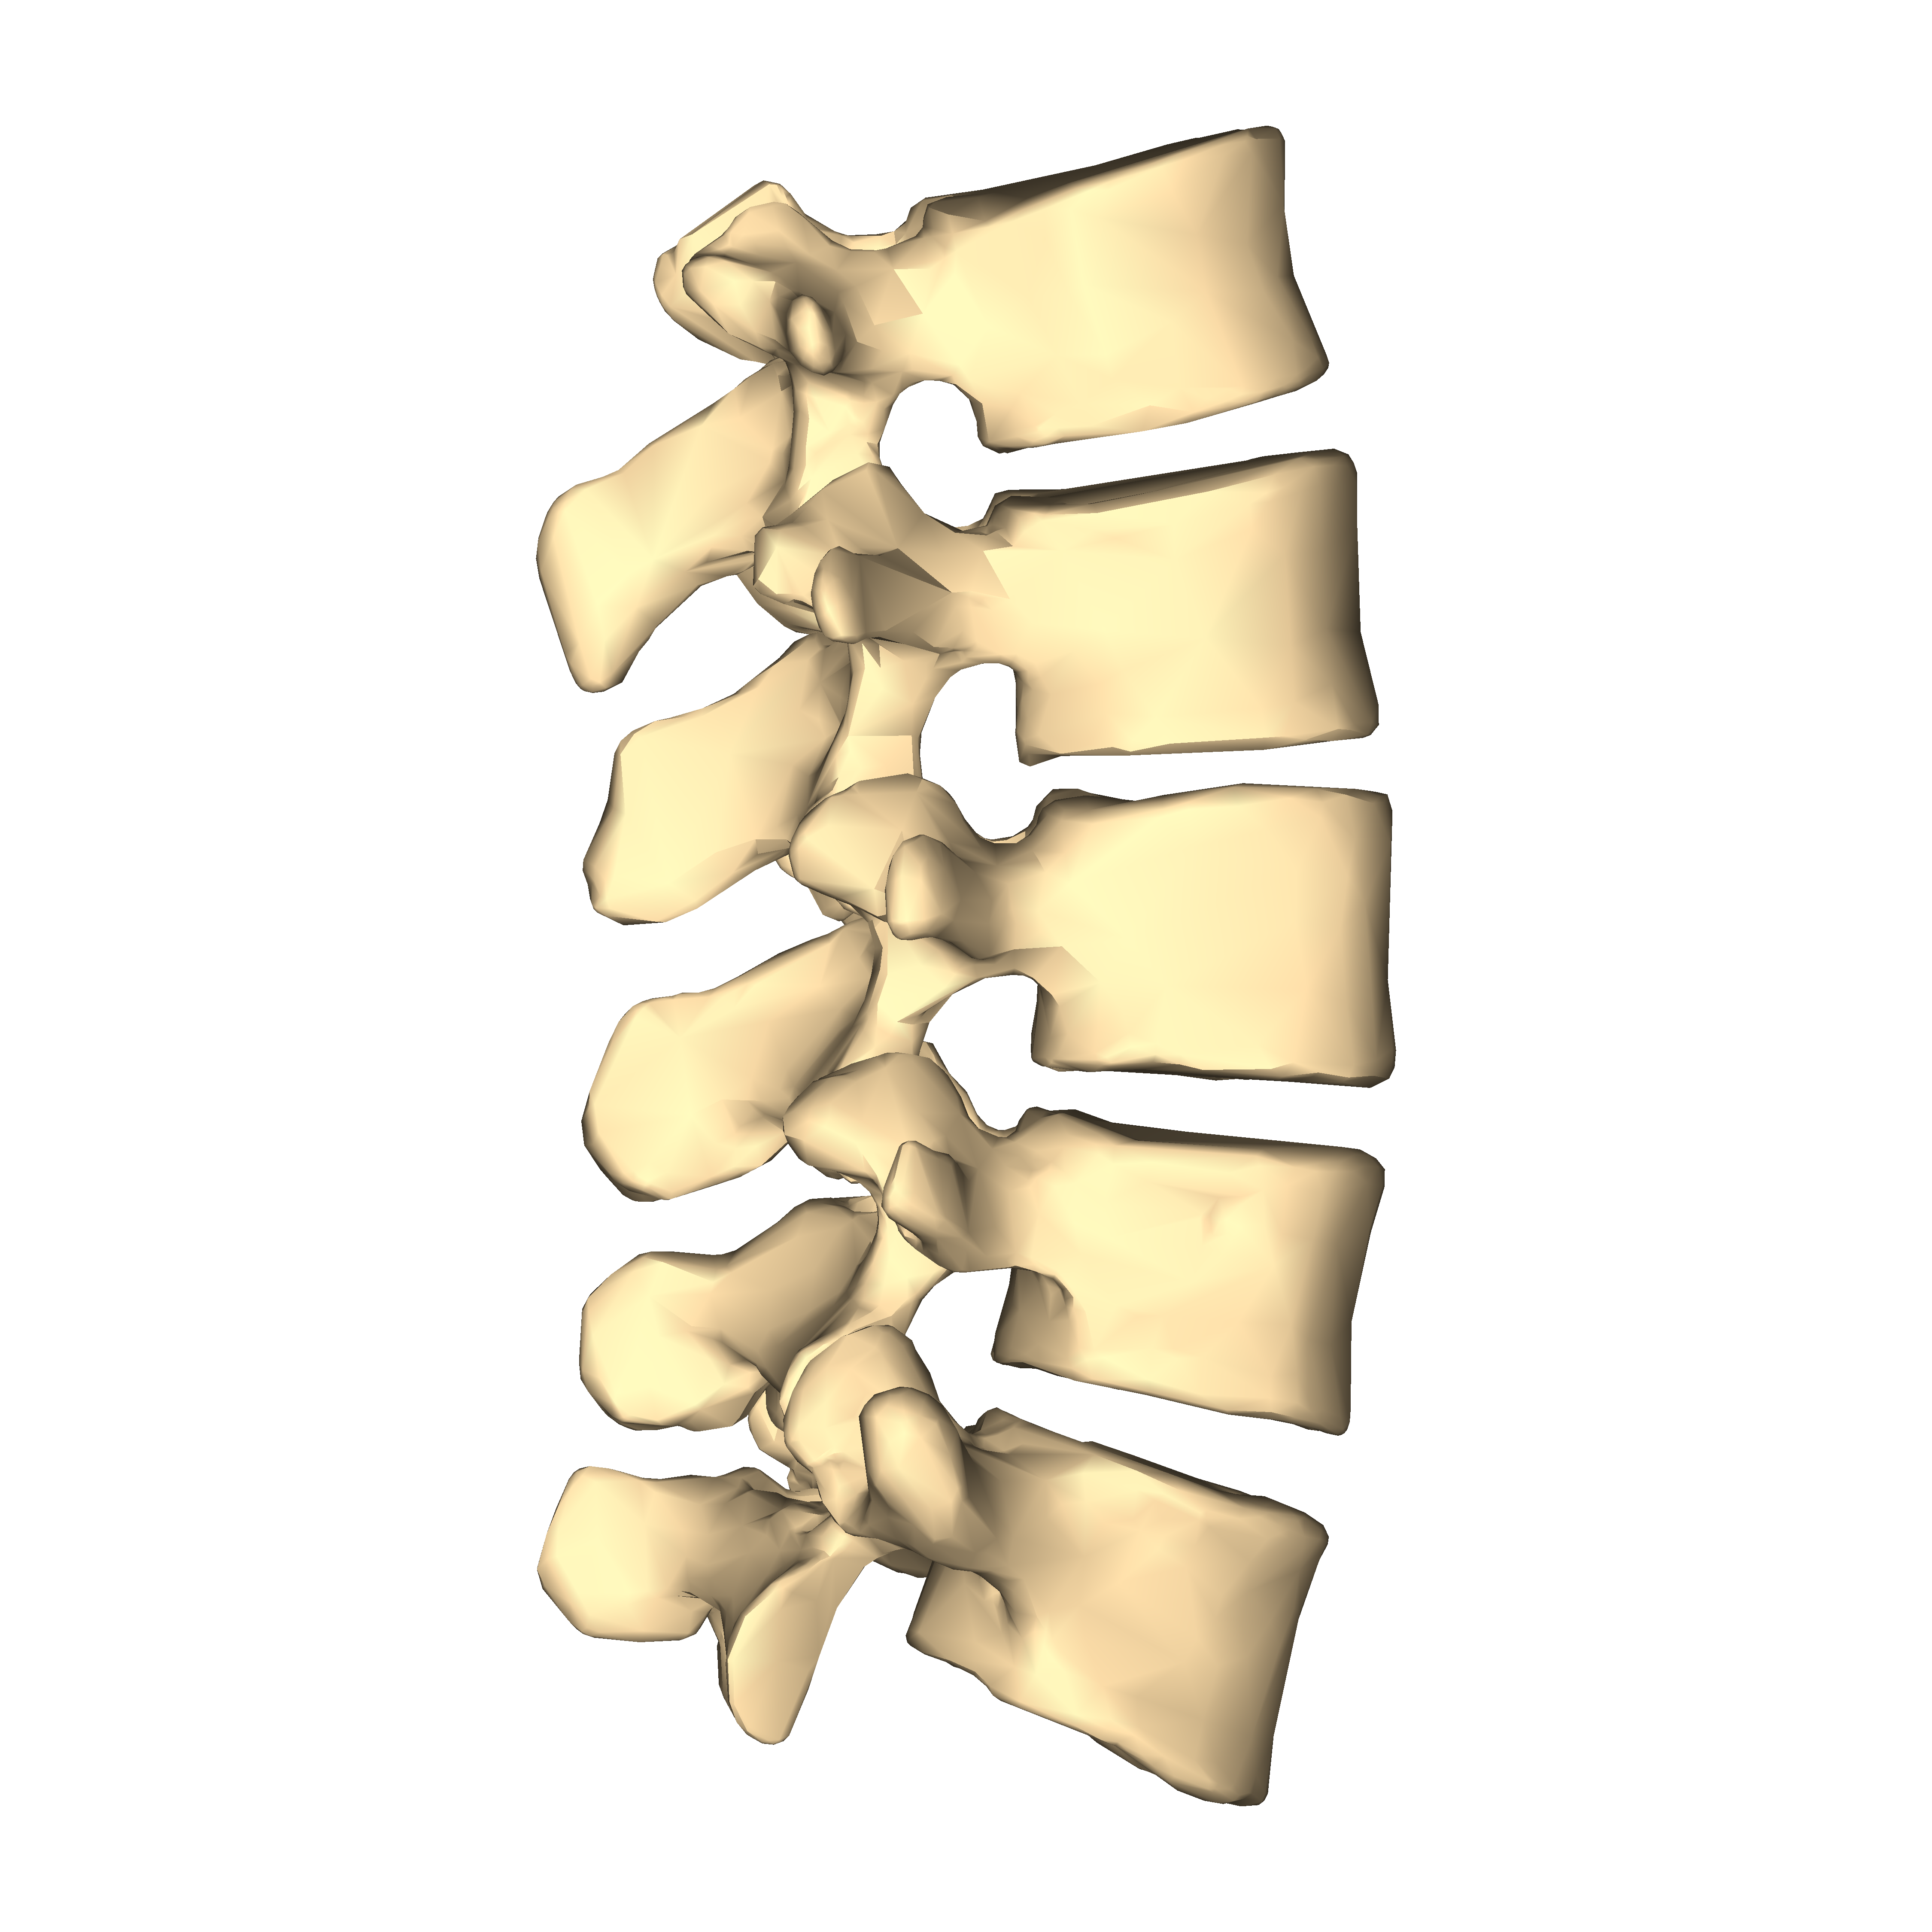

Estenosis foraminal lumbar, hernia discal lumbar, síndrome facetario, lumbalgia, Protusión discal, etc. Más de la mitad de las dolencias relacionadas con el dolor crónico están localizadas en la zona lumbar. En Instituto Ordóñez te ofrecemos técnicas pioneras con aparatología propia y de la mano de los mejores protocolos exclusivos para mejorar tus dolores de espalda.

El dolor lumbar: la epidemia silenciosa

La zona lumbar acapara más del cincuenta por ciento de las dolencias relacionadas con el dolor recurrente. Estas patologías son altamente limitantes, generan estrés y reducen la calidad de vida en las personas.